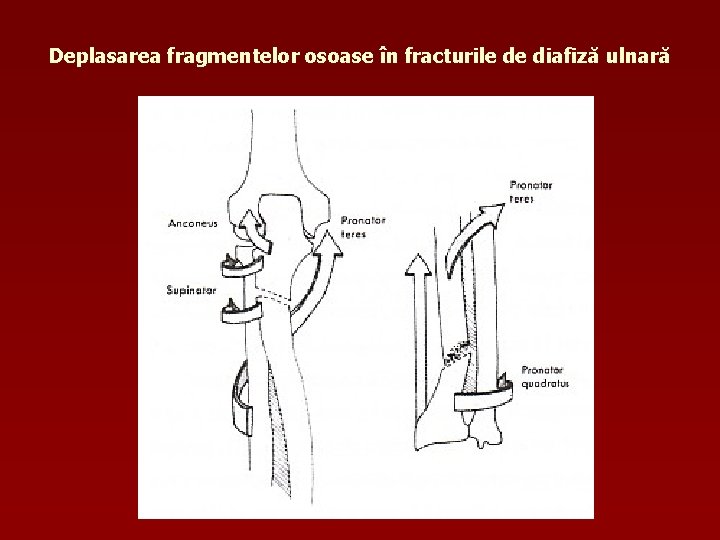

Deplasarea fragmentelor osoase în fracturile de diafiză ulnară